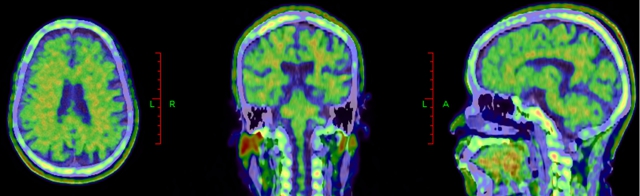

利用脑部影像学技术,如MRI可以发现特异区域的萎缩;PET-CT扫描,可以检测大脑中的异常蛋白质堆积或其他结构变化(见下图)。

阿尔茨海默病患者淀粉样蛋白PET,可显示大脑皮层广泛β-淀粉样蛋白沉积